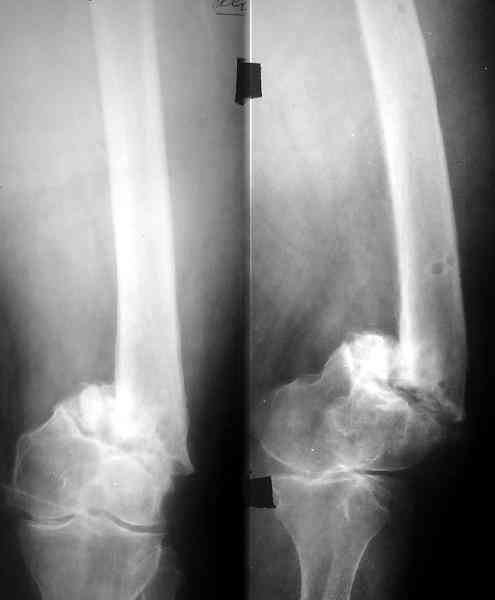

Пример подобного ложного сустава в приложении.